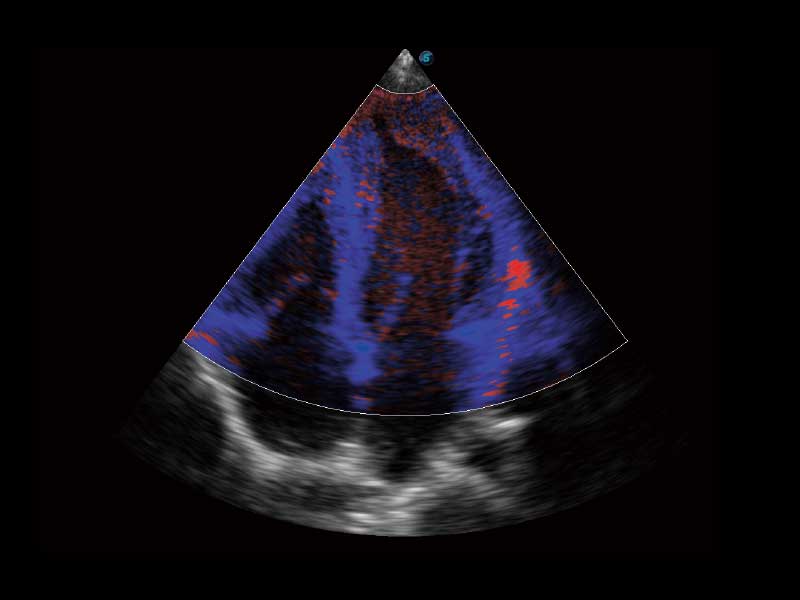

μ-Scan微米成像、空间复合成像、高分辨率血流成像。

在实时扫查过程中,一键快速存储实时影像,无须冻结图像中断扫查。可存储长时间和大容量电影文件,提供更为精准的术中、急诊等临床应用。